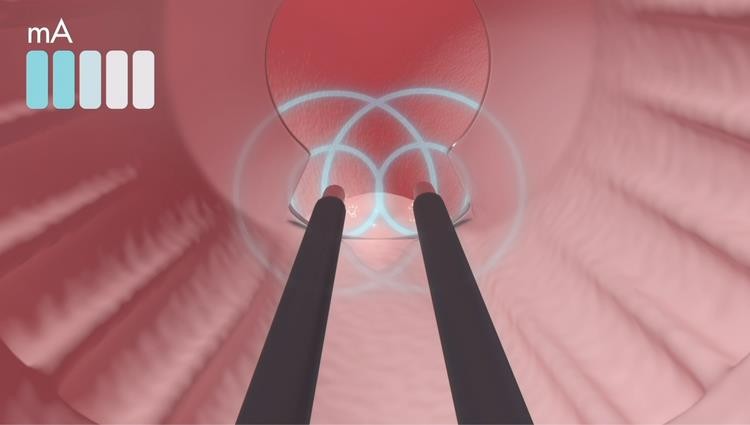

THE EXROID PROCEDURE IN DETAIL

A single-use probe is used to gently apply a low direct current (up to 16mAmp) to the haemorrhoid. The probe is placed in direct contact with the base of the haemorrhoid, targeting the blood vessels which feed it. No tissue penetration of any kind is required.

This causes a chemical reaction within the vascular feeding vessels, releasing hydrogen gas and hydroxyl ions:

This creates a strong alkaline environment that causes denaturation of protein, thrombosis of the capillary feeding vessels, and a chemical cauterisation within the vascular feeding vessels of the haemorrhoid. This is not a heat treatment.

As treatment progresses, the haemorrhoid visibly shrinks. With the blood flow to the haemorrhoid interrupted, the haemorrhoid continues to shrink for a week, or longer following treatment. As the haemorrhoid shrinks during and after treatment, symptoms are relieved. In many cases, the patient will feel relief immediately after the procedure. The procedure takes up to 10 minutes per haemorrhoid depending on what grade and size they are. eXroid recommends that up to three haemorrhoids can be treated in single treatment session.

The amperage delivered to the base of the haemorrhoid can be varied by pressing the ‘up’ and ‘down’ buttons on the hand control. Communicating with the patient during treatment, the eXroid specialist can regulate the current to minimise any discomfort for the patient. If the patient can tolerate a higher current, the treatment will be shorter.